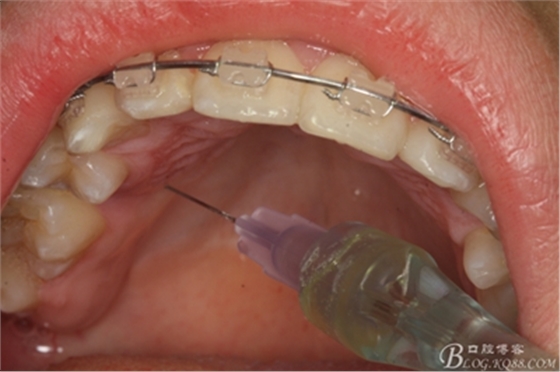

圖5.涂布表面麻醉劑

圖6.唇側(cè)局部無痛浸潤(rùn)麻醉

圖7.腭側(cè)無痛浸潤(rùn)麻醉